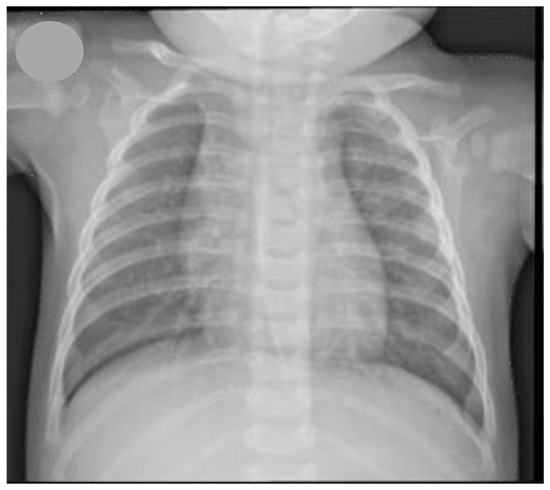

2. Case Presentation

3. Discussion